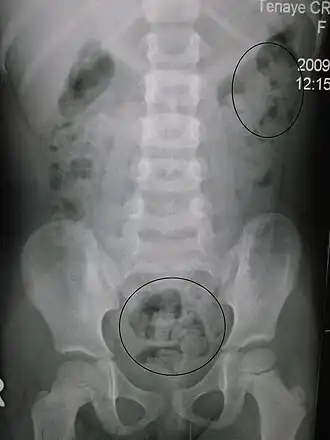

| Raio-x de obstipação numa criança. Os círculos assinalam os locais opacos de aglomeração de fezes. | |